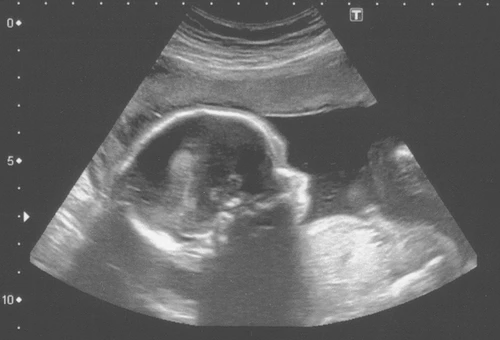

MADRID, 15 Oct. 13 / 09:36 am (ACI/Europa Press).- El diputado de Unión del Pueblo Navarro (UPN) Carlos Salvador ha presentado en el Congreso una iniciativa para reformar la Ley del Aborto de 2010 y que sea obligatoria la muestra de una ecografía del 'nasciturus', o concebido no nacido, antes de que la mujer decida interrumpir de forma voluntaria su embarazo porque "una imagen vale más que mil palabras".

Así, UPN propone añadir una nueva letra al articulado de la vigente ley para que, en aquellos casos en los que las mujeres opten por la interrupción del embarazo en las primeras 14 semanas de gestación, recibirán en un sobre cerrado, y junto a la lista de ayudas públicas disponibles para las gestantes y la cobertura sanitaria durante el embarazo que determina la ley, una ecografía del 'nasciturus'.

Salvador dice que, siguiendo las recomendaciones a favor de la protección de la maternidad del citado dictamen, "parece oportuno" plantear la entrega de una imagen del no nacido a través de una ecografía que muestre la "realidad vital y humana de su existencia" y que, unida al resto de la documentación, sirva a la madre y, en su caso, al padre, para poder tomar una decisión "con toda la información relevante a su alcance y sin censuras".

Es más, indica que la presente iniciativa se enmarca dentro de aquellas propuestas que buscan dotar de un contenido concreto al derecho a la información. "Lo que se pretende en este caso es añadir a la información que explicita la actual Ley Orgánica de Interrupción Voluntaria del Embarazo una ecografía, por el medio técnico que se estime más oportuno, es decir, una imagen del ser humano no nacido", apunta.